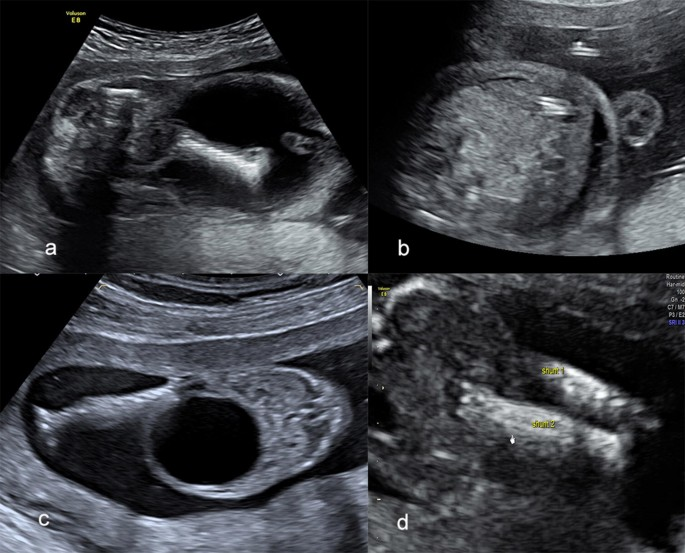

Once enlargement of the bladder is detected, the next step involves careful evaluation and monitoring. A detailed targeted ultrasound is done to examine the kidneys, ureters and bladder outlet and to look for any additional structural or chromosomal abnormalities.

The management of fetal megacystis depends on its underlying cause and severity. In early and mild cases, regular monitoring is often all that’s required. Continuous ultrasound scans help track whether the bladder returns to its normal size or if the condition progresses.

If an obstruction is confirmed and the condition appears severe, more active intervention may be considered. One potential option is vesicoamniotic shunting, a minimally invasive procedure in which a small tube is inserted to drain urine from the bladder into the amniotic cavity. This can help relieve pressure on the kidneys and allow better lung development.